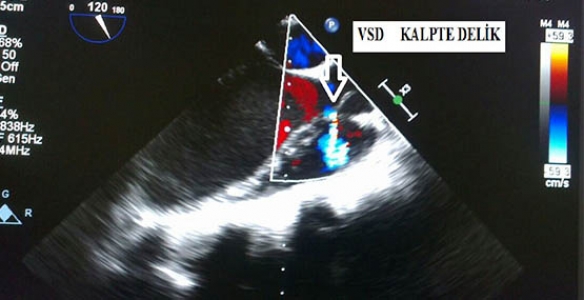

Ameliyat hakkında bilgi veren SAÜ Tıp Fakültesi Kardiyoloji Bölüm Başkanı Prof. Dr. Hüseyin Gündüz, “Geçen hafta kalbinde delik olan 18 yaşında bir genç kızımız, başka merkezlerde yapılmaya cesaret edilmediği için ünitemize tedavi amacıyla sevk edildi. Dekanımız Prof. Dr. Ramazan Akdemir liderliğinde bir ekip tarafından, peruktan (kapalı) yolla ameliyatla, yarım saatten kısa süre içinde başarılı bir şekilde tedavisini tamamladık. Hastamızın sağlık durumu şu an gayet iyi ve nefes darlığı, çarpıntı gibi yakınmaları kısa sürede geçti” dedi.